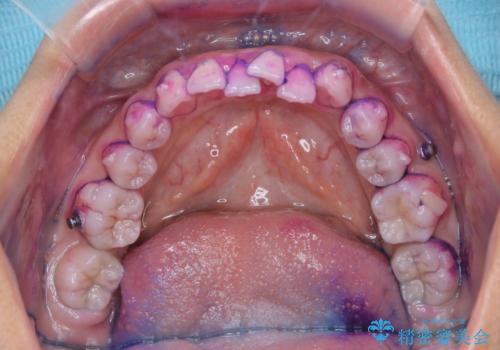

染め出し液を使ってプラークを染め出すことにより、普段の歯みがきで磨き残している場所を目で確かめることができます。

日々の歯磨きを上達するには、まずどこが磨けていないか認識することが大切です。

また、矯正で歯の移動があると今までなかったところに隙間が出てきたり、ガタつきが解消されてきたりすることで、お口の中の環境が変わります。